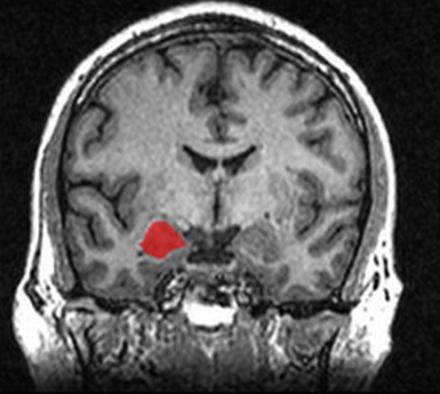

За наши эмоции отвечает лимбическая система головного мозга. Именно она выдает вегетативные и эндокринные реакции (выброс гормонов, учащение сердцебиения и т.д.) в ответ на раздражитель. Что касается такой эмоции, как агрессия, эта реакция возникает в крошечном органе лимбической системы, расположенном в глубине височной доли – миндалевидном теле.

В норме нейроны этой зоны возбуждаются при сильной стимуляции – когда человека действительно «достали» и нужно постоять за себя. Отстоял себя – и нейроны лимбической системы успокоились. У человека с психологической травмой или эмоциональным истощением нейроны миндалевидного тела постоянно находятся в состоянии «боевой готовности» – возбуждены.

Наряду с гиперактивностью нейронов миндалевидного тела, у раздражительных людей наблюдается пониженная активность нейронов префронтальной коры (передней части лобных долей), а эта зона, между прочим, отвечает за механизмы подавления агрессии – контроль эмоциональных и поведенческих реакций.

Когда активность лобных долей подавлена, а миндалевидное тело возбуждено, любой слабый раздражитель вызывает бурную реакцию. О вреде этой реакции мы рассказали, но пока так и не ответили на главный вопрос – что делать?